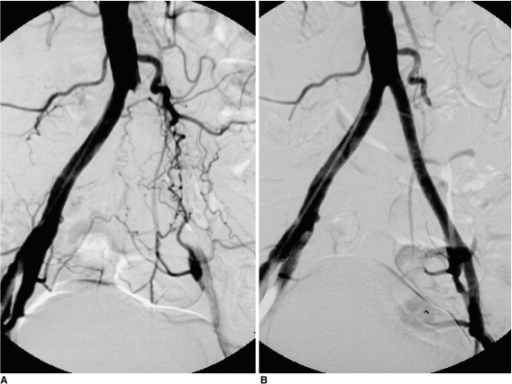

Απεικονιστικές εξετάσεις για τη διερεύνηση της διαλείπουσας χωλότητας αποτελούν το έγχρωμο duplex (triplex), η αξονική αγγειογραφία, η μαγνητική αγγειογραφία και η ψηφιακή αφαιρετική αγγειογραφία.

Σε περιπτώσεις διαλείπουσας χωλότητας μη περιοριστικού τύπου συνήθως η θεραπεία είναι συντηρητική. Αυτή περιλαμβάνει φαρμακευτική αγωγή, ρύθμιση παραγόντων κινδύνου, διακοπή του καπνίσματος και επιτηρούμενο πρόγραμμα άσκησης. Σε περιπτώσεις κρίσιμης ισχαιμίας ή σοβαρής διαλείπουσας χωλότητας η αντιμετώπιση είναι συνήθως επεμβατική, είτε με αγγειοπλαστική με ή χωρίς stent, ή χειρουργική.